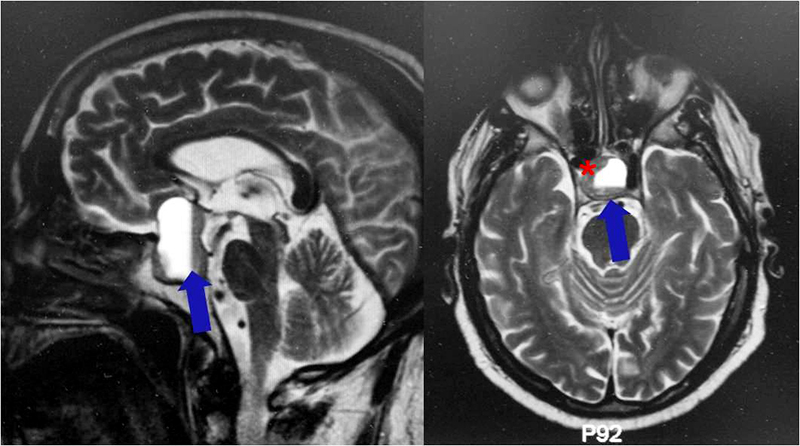

L'ipofisi o ghiandola pituitaria è una ghiandola endocrina situata alla base del cranio, nella sella turcica dell'osso sfenoide.

- Bifasicità: Nella fase di CA si hanno alterazioni ormonali ipofisarie, agitazione, insonnia, disturbi emocoagulativi, psichicamente maniacale. Nella fase PCL si ha un ristabilimento dell'equilibrio ormonale e del sistema neurovegetativo. Se è concomitante la sindrome del Profugo (Vedi → Profugo, sindrome del) si possono avere problemi di scarico liquorale e idrocefalo conseguente